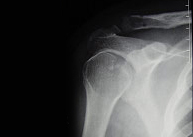

Las luxaciones acromioclaviculares son producidas por traumatismos en el hombro y producen la separación entre la clavícula y el acromion. La fuerza deformante puede llegar al hombro de forma directa (impacto sobre el hombro) o de forma indirecta tras caída sobre la mano con la extremidad extendida y transmisión del impacto al hombro.

En función de la separación entre los huesos que forman la articulación (acromion y clavícula) el tratamiento puede ser conservador o quirúrgico.

Cuando la separación es grande y la posibilidad de restauración por métodos conservadores es imposible proponemos una rápida y mínima intervención para la reparación articular definitiva